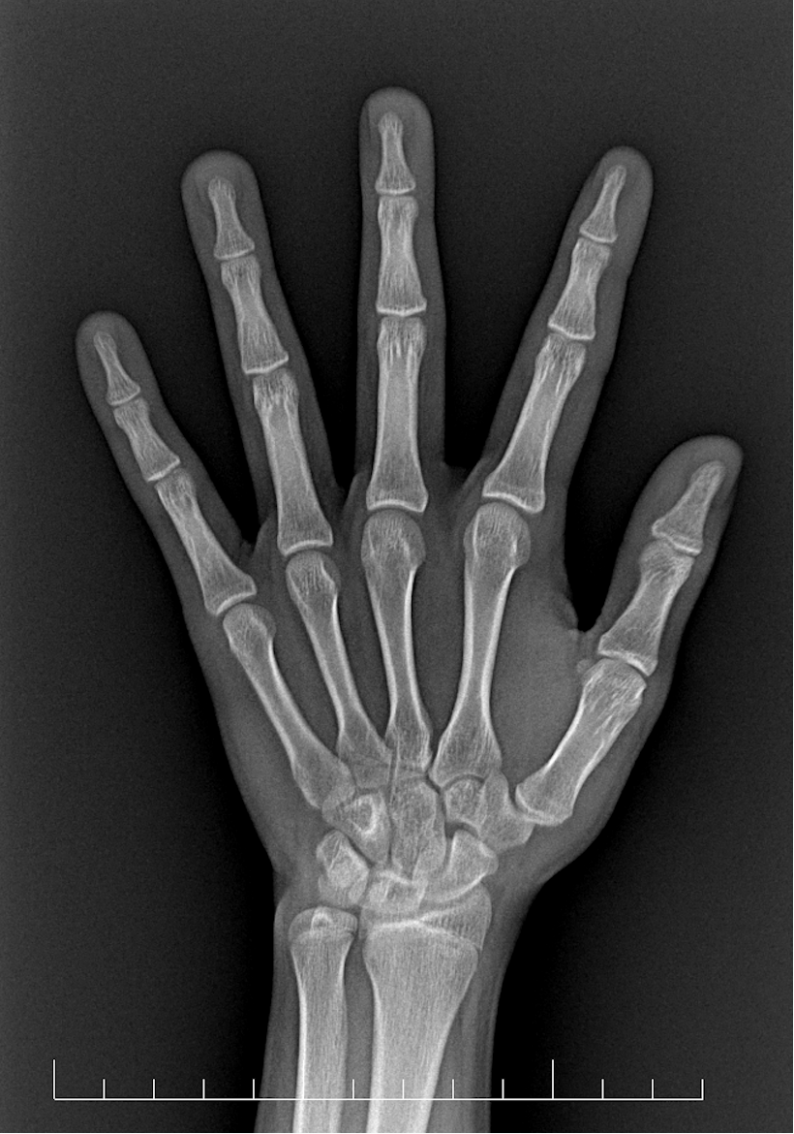

小杨父亲告诉医生:孩子从小在同龄孩子中偏矮,两年前的时候,孩子的身高突然蹿的很快,那时候在别的医院测过骨龄,结果是正常的。就默认觉得只要孩子身高长的快,骨龄也是正常的,后面就可以不用操心了。结果到了最近几个月,发现孩子身高不怎么长了,心里开始着急起来,特地带孩子来医院看一下。等拿到骨龄评估报告,孩子父亲沉默了,骨龄提示小杨已超 16 岁,骨骺接近闭合,生长空间所剩无几。孩子长到 170 cm 的梦想,瞬间成为泡影。 父亲懊悔不已:「要是早点继续监测,早点干预,结果会不会不一样?」

你可能每月给孩子量身高,记录成长曲线,但你可能忽略了一个更关键的指标——骨龄。什么是骨龄?简单说,就是骨骼的「身份证年龄」。每个孩子都有两个年龄:生活年龄:从出生那天算起,过了几个生日就是几岁;骨骼年龄:骨骼实际发育成熟的程度。 这两个年龄本该步调一致,但现实中却常常「错位」。就像小杨,生活年龄 14 岁,骨骼年龄却已跑到 16 岁,提前「成熟」了。

为什么骨龄比身高数字更重要?孩子的生长就像一场有限时的赛跑。身高告诉你现在跑了多远,骨龄却告诉你:离终点还有多远?剩余时间有多少?有些孩子看似长得快(像两年前的小杨),但可能是骨龄跑得更快,生长周期缩短,最终反而长不高。有些孩子长得慢,但骨龄也慢,反而有「后发优势」。只关注身高不关注骨龄,就像只看车速不看油表,可能突然发现「没油了」,但为时已晚。

骨龄是动态变化的,尤其是快速生长期和青春期,可能几个月就有很大不同。孩子的生长只有一次,骨骺一旦闭合,任何方法都无法再让孩子长高。那些所谓「23 岁还窜一窜」的说法,对绝大多数人只是美好传说。科学监测 + 及时干预 = 最大化遗传潜力!